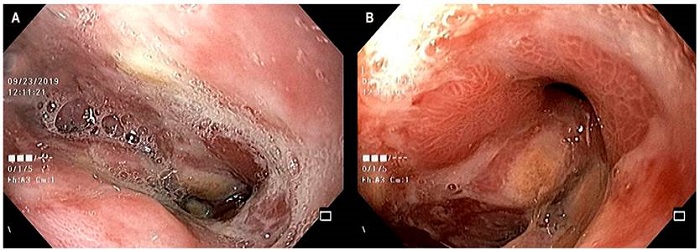

Dado la persistencia de una fístula de 5 mm sobre anastomosis se realiza terapia Endo-Vac con esponja de GranuFoamTM, conectada a un sistema de drenaje intermitente, con una presión negativa de 100 mm Hg (Figura 2). Conjuntamente se llevó a cabo una yeyunostomía laparoscópica. Se realiza recambio de esponja a los 7 días y se observa una reducción del defecto fistuloso. A las 2 semanas de inicio de la terapia se logra la adecuada cicatrización, sin evidencia de fístula. Se extrae la esponja y la sonda nasogástrica con asa de 30 mm sin complicaciones. Control endoscópico al mes y 3 meses de finalizar la terapia Endo-Vac. Anastomosis con cambios inflamatorios y disminución de la luz en 30 %, por efecto de angulación y no por estenosis, lo que permitió el paso fácil del equipo (Figura 3). Se indicó manejo con inhibidor de bomba de protones, y se logró una mejoría de la disfagia, sin dolor torácico.